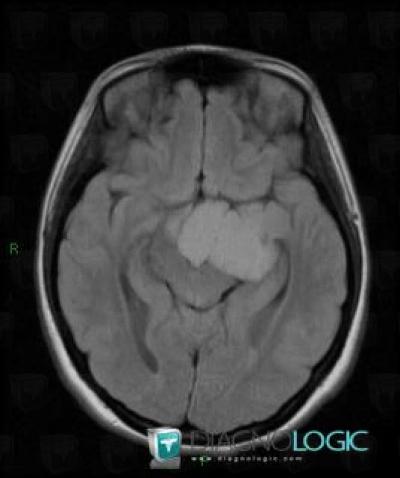

Craniopharyngiome, Hémisphères cérébraux, IRM

Voici les informations spécifiques à l'image clé ci dessus:

- Diagnostic Craniopharyngiome, Localisation(s) Hémisphères cérébraux, comportant les gammes Masse intracérébrale, Lésion intracérébrale en hypersignal T2 ou FLAIR